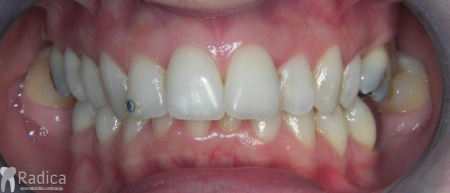

Slučaj 2: ispravljanje kompresije Invisalign full terapijom- u ovom slučaju je izvađen jedan donji sjekutić